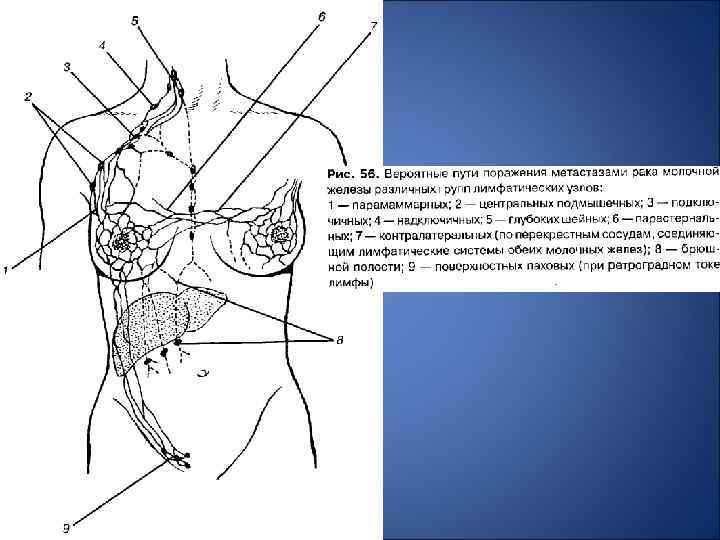

Аномалии молочной железы: медицинские примеры и визуализация

Раздел: Мудрость в деталях